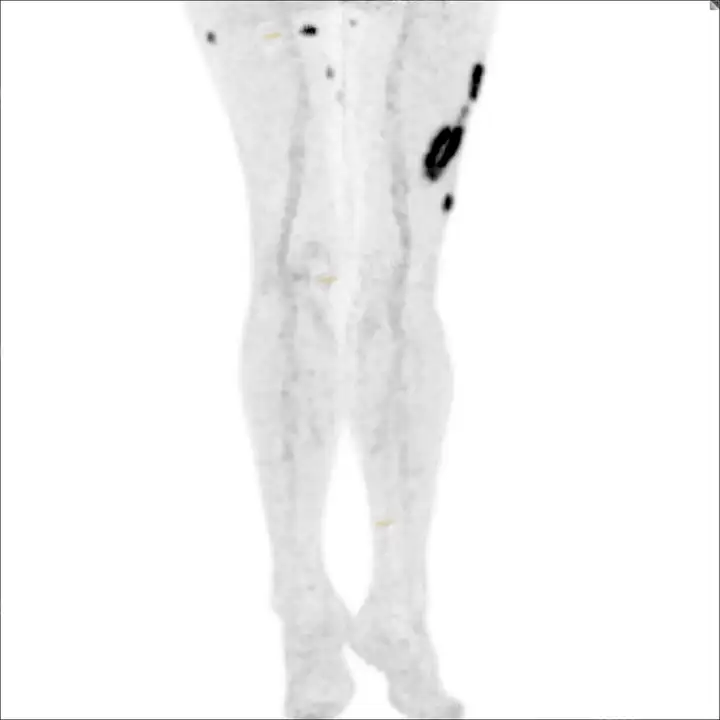

PETCT检查所示:图1、3-17全身多处(双上臂、胸背部、左侧乳腺、左侧腰部、腹壁、双侧臀部及双侧大腿)皮肤下结节及肿块样软组织密度灶,FDG代谢不同程度增高,双侧颈部、左侧锁骨区、纵隔内(1区)及双侧腋窝多发肿大淋巴结,FDG代谢明显增高,符合皮肤来源淋巴瘤。